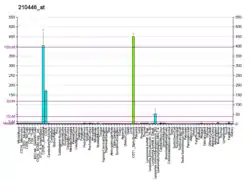

GATA-binding factor 1 or GATA-1 (also termed Erythroid transcription factor) is the founding member of the GATA family of transcription factors. This protein is widely expressed throughout vertebrate species. In humans and mice, it is encoded by the GATA1 and Gata1 genes, respectively. These genes are located on the X chromosome in both species.[5][6]

GATA1 regulates the expression (i.e. formation of the genes' products) of an ensemble of genes that mediate the development of red blood cells and platelets. Its critical roles in red blood cell formation include promoting the maturation of precursor cells, e.g. erythroblasts, to red blood cells and stimulating these cells to erect their cytoskeleton and biosynthesize their oxygen-carrying components viz., hemoglobin and heme. GATA1 plays a similarly critical role in the maturation of blood platelets from megakaryoblasts, promegakaryocytes, and megakaryocytes; the latter cells then shed membrane-enclosed fragments of their cytoplasm, i.e. platelets, into the blood.[5][7]

GATA1 was first described as a transcription factor that activates the hemoglobin B gene in the red blood cell precursors of chickens.[30] Subsequent studies in mice and isolated human cells found that GATA1 stimulates the expression of genes that promote the maturation of precursor cells (e.g. erythroblasts) to red blood cells while silencing genes that cause these precursors to proliferate and thereby to self-renew.[31][32] GATA1 stimulates this maturation by, for example, inducing the expression of genes in erythroid cells that contribute to the formation of their cytoskeleton and that make enzymes necessary for the biosynthesis of hemoglobins and heme, the oxygen-carrying components of red blood cells. GATA1-inactivating mutations may thereby result in a failure to produce sufficient numbers of and/or fully functional red blood cells.[5] Also based on mouse and isolated human cell studies, GATA1 appears to play a similarly critical role in the maturation of platelets from their precursor cells. This maturation involves the stimulation of megakaryoblasts to mature ultimately to megakaryocytes which cells shed membrane-enclosed fragments of their cytoplasm, i.e. platelets, into the blood. GATA1-inactivating mutations may thereby result in reduced levels of and/or dysfunctional blood platelets.[5][7]